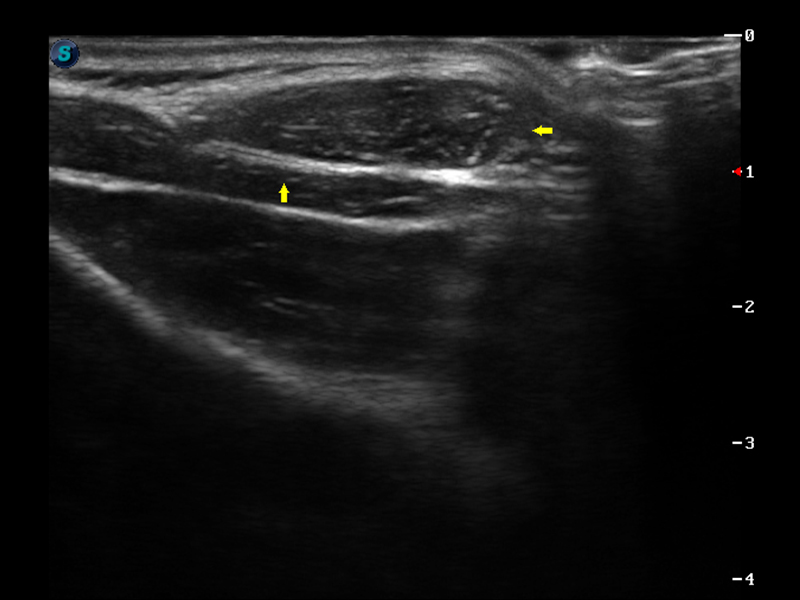

实时宽景成像